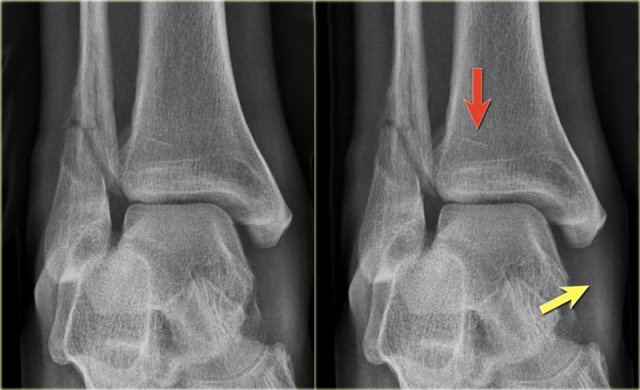

Click to enlarge Click to enlarge

Example 4

• Basic interpretation

Fracture of the lateral malleolus starting anteriorly at the level of the joint extending proximally posteriorly.

• Classification

The fracture is classified according to Weber as a type B fracture.

According to Lauge Hansen the oblique fibular fracture indicates that this is a Supination Exorotation injury stage 2 or higher.

• Re-examination

Look for stage 3 and stage 4.

There are subtle findings which indicate a fracture of the posterior malleolus. Normally you probably would not have noticed these.

On the lateral view the posterior cortex of the tibia is interrupted indicating a fracture (blue arrow).

Even on the AP-view there are subtle findings that indicate a fracture (red arrows).

There is a widened medial clear space, which indicates a rupture of the medial collateral band, i.e. stage 4.

• Final report

Weber B fracture. According to Lauge-Hansen this is a SER stage 4.

This is an unstable fracture with dislocation that needs surgical repair.